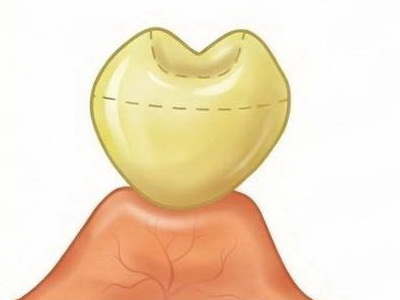

Răng giả nhịp cầu dạng yên ngựa (Saddle Pontic)

- Tiếp xúc: Mặt đáy răng giả có dạng lõm, phủ kín và ôm trọn sống hàm còn lại, tương tự như yên ngựa đặt trên lưng ngựa.

- Đặc điểm: Tạo ra vùng tiếp xúc rộng và lớn với niêm mạc ở cả mặt ngoài và mặt trong của sống hàm.

- Thực tế trong lâm sàng: Nhịp cầu loại này có diện tiếp xúc với niêm mạc quá rộng. Dù nhìn bên ngoài rất thẩm mỹ vì ôm sát sống hàm, nhưng nó tạo ra một “vùng chết” không thể làm sạch bằng bàn chải hay chỉ nha khoa dẫn đến vi khuẩn tích tụ dưới đáy nhịp cầu sẽ gây viêm nướu mạn tính, hôi miệng và tệ nhất là tiêu xương ổ răng của các răng trụ. Mình khuyên anh em nên tránh nhịp cầu loại này nếu không muốn bệnh nhân quay lại bắt đền vì cầu răng hôi và viêm..